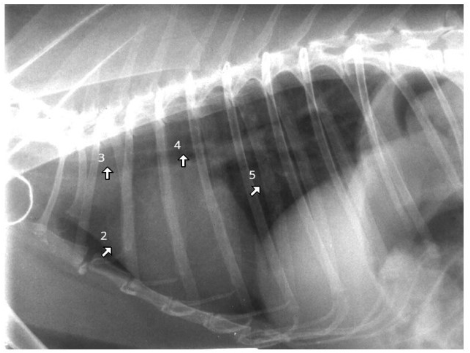

what species

what are the numbers

rabbit

2= cardiac silhouette

= trachea

where trachea bifurcates to go into different bronchi

caudal vena cava